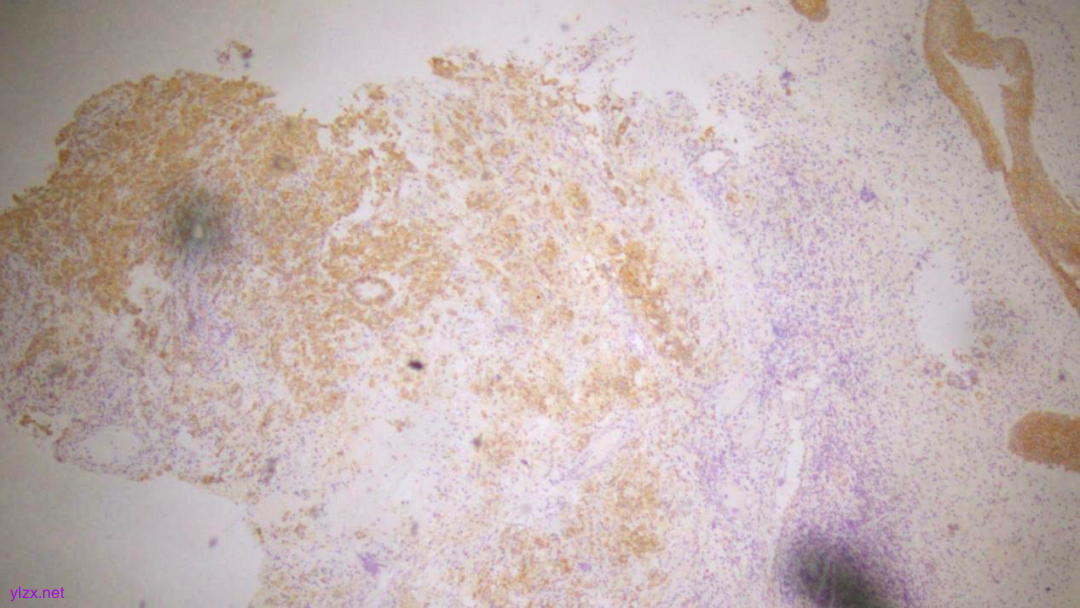

IHC结果:

CK(AE1/AE3)(+)、GATA3(+)、P120(浆+)、E-Cadherin(-)、CK7(+)、CK-H(+)、CAM5.2(+)、CK20(-)、CEA(poly)(-),P53(约40% 弱+),Ki-67(约1%+)

AE1/AE3(弥漫强+)

GATA-3(+)

P120(浆+)

E-Cadherin(-)

CEA(少量+)

CK7(弥漫强+)

ki-67(个别细胞+)